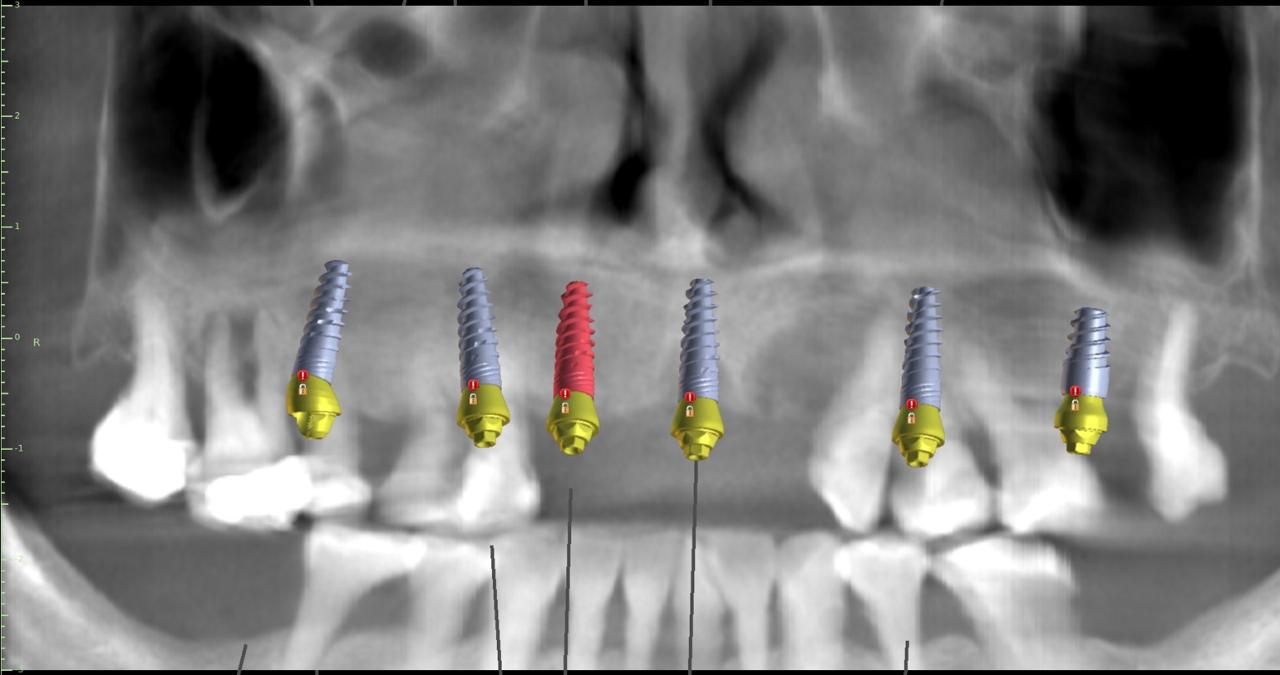

La intervención se realizó bajo anestesia general y contempló la extracción de la totalidad de los dientes del maxilar superior debido a una enfermedad periodontal avanzada, junto con la instalación simultánea de seis implantes dentales mediante cirugía guiada por planificación digital. En este caso, no se efectuó carga inmediata: el plan considera una carga temprana dentro del proceso de rehabilitación.

Uno de los aspectos más destacados fue que, en el mismo acto quirúrgico, se realizó la toma de la impresión para enviar a confeccionar una estructura provisoria completa (con la totalidad de los dientes maxilares), diseñada y elaborada mediante un proceso digital, lo que permite acortar tiempos y aumentar la precisión en etapas clave del tratamiento.